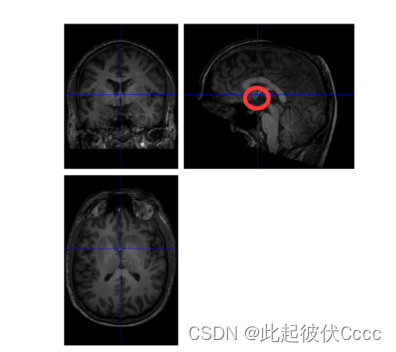

2.2 检查图像,调整原点

首先就是需要我们自己手动调整一下结构像,打开spm,点击spm首页的PET&VBM,然后点Display,摆正每个被试的 T1 数据,并使 AC-PC 的连线水平。

手动将蓝色十字线的交叉点放到大概下面这个位置,即前联合的位置。